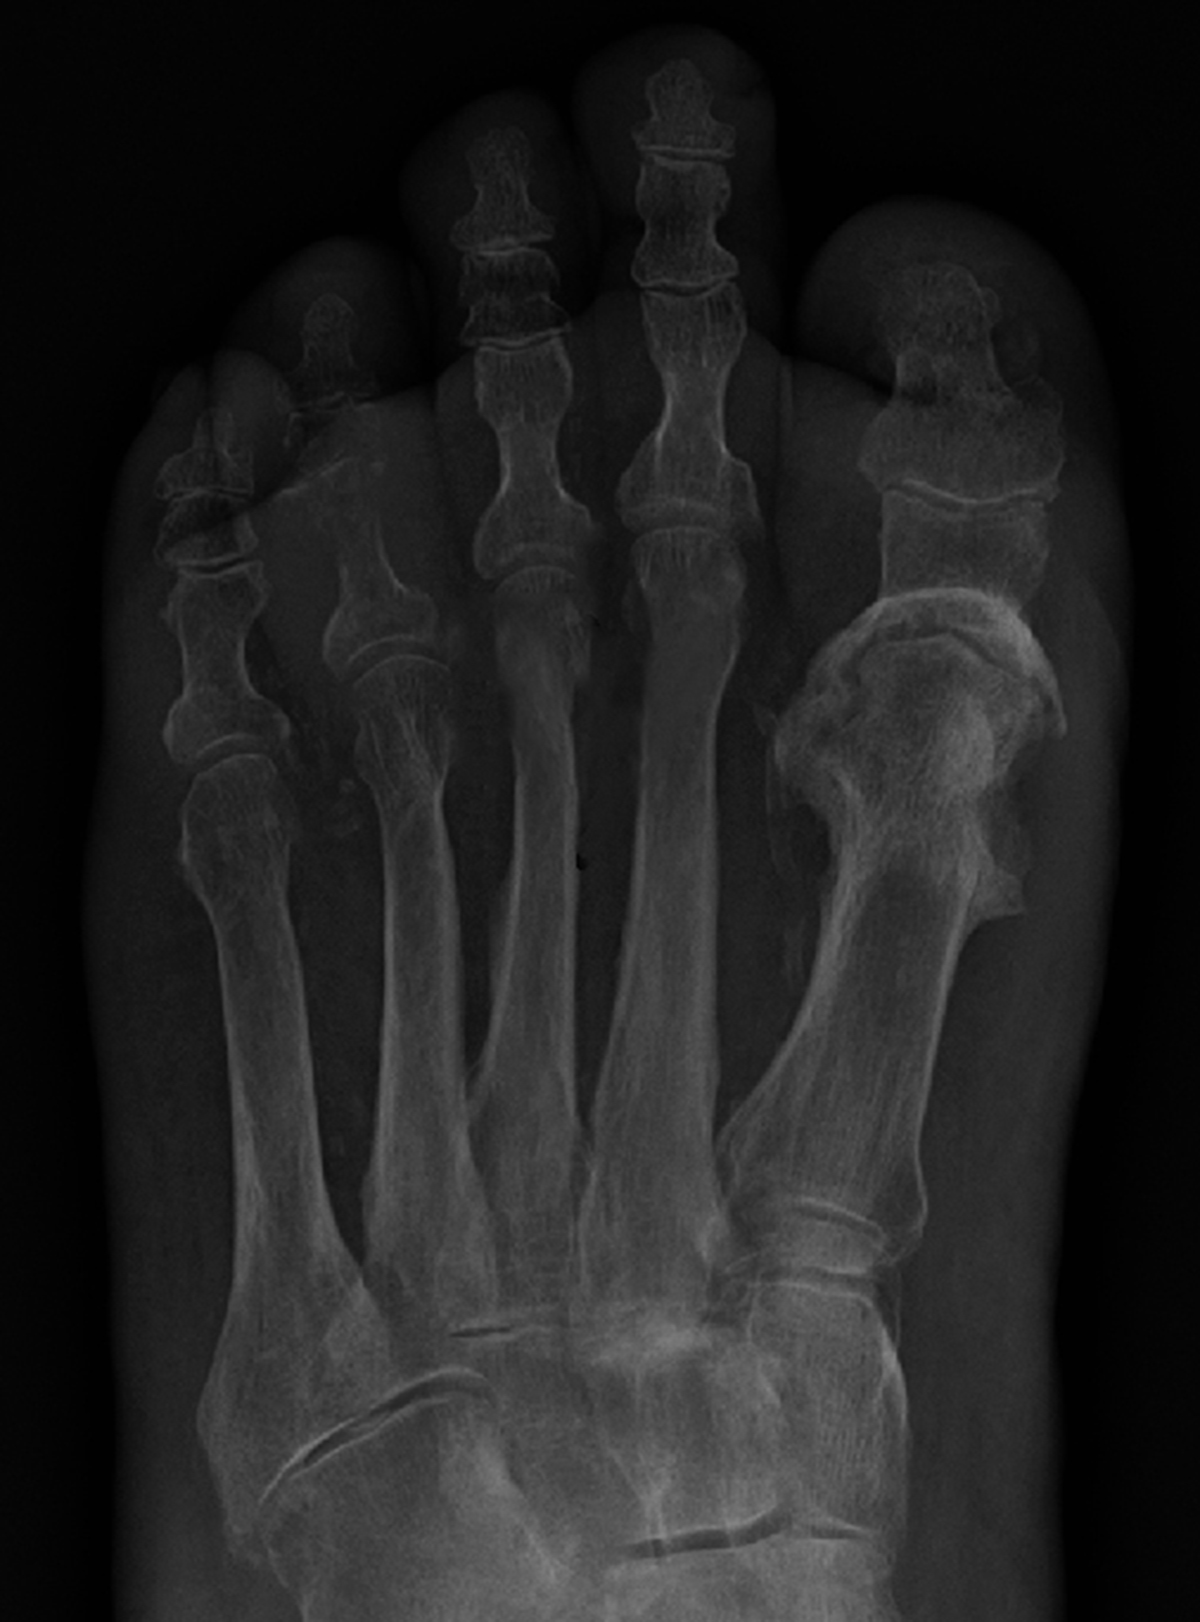

Osteomielita este o infecție a oaselor și a măduvei osoase, care afectează de obicei zonele situate în apropierea articulațiilor și apare mai frecvent la copii sau adolescenți.

Această afecțiune se manifestă adesea în oasele lungi, cum ar fi tibia, femurul și humerusul.